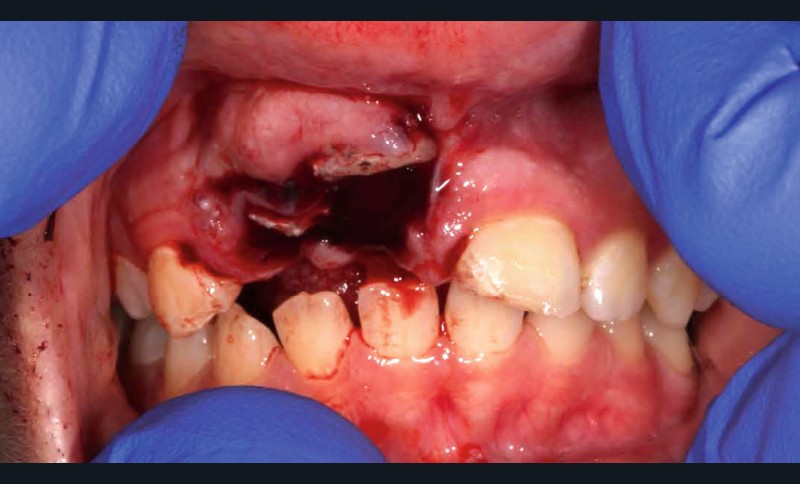

Yasmine, une adolescente de 14 ans et demi, en bonne santé générale, consulte en urgence vers 10h30, à la suite d’une chute s’étant produite le matin même en allant à l’école vers 8h. Les figures 1 et 2 montrent respectivement les vues cliniques et radiographiques. La mère nous rapporte un antécédent de trauma sur les incisives centrales, il y a quelques années.